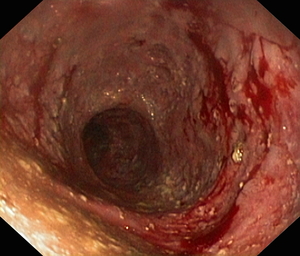

Uchyłki jelita – omówienie aktualnego stanu wiedzy